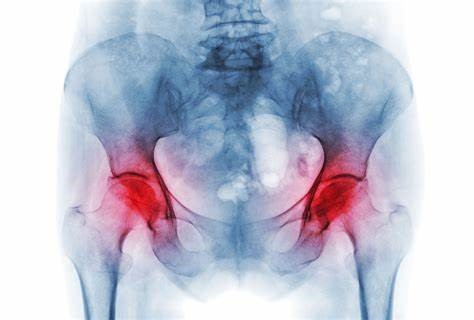

ادامه مطلبیک بیماری است که استخوانهای بلند را درگیر میکند. بخصوص سر استخوان ران. سر استخوان ران یا قسمت توپی شکل مفصل ران خون کمتری دریافت میکند و ازآنجاییکه استخوان بافت زنده است هنگامیکه این خون بهاندازه کافی کاهش یابد، استخوان میمیرد و اصطلاحا سیاه میشود.پس از مرگ استخوان ران، سر استخوان ران فرو میرود و…